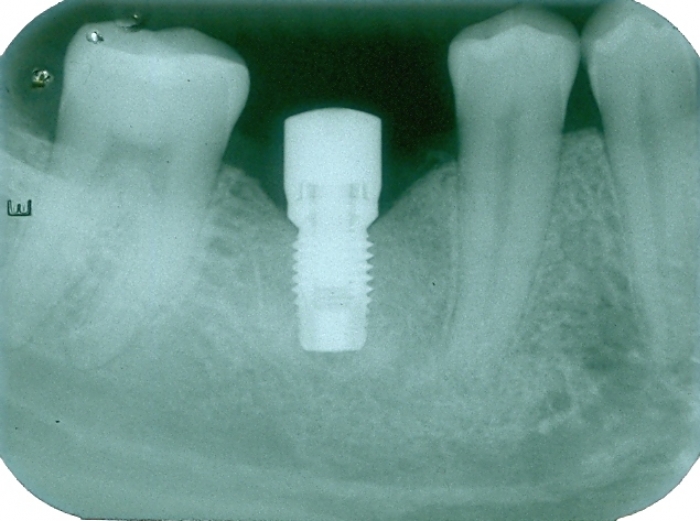

Raio X do implante instalado, com cicatrizador